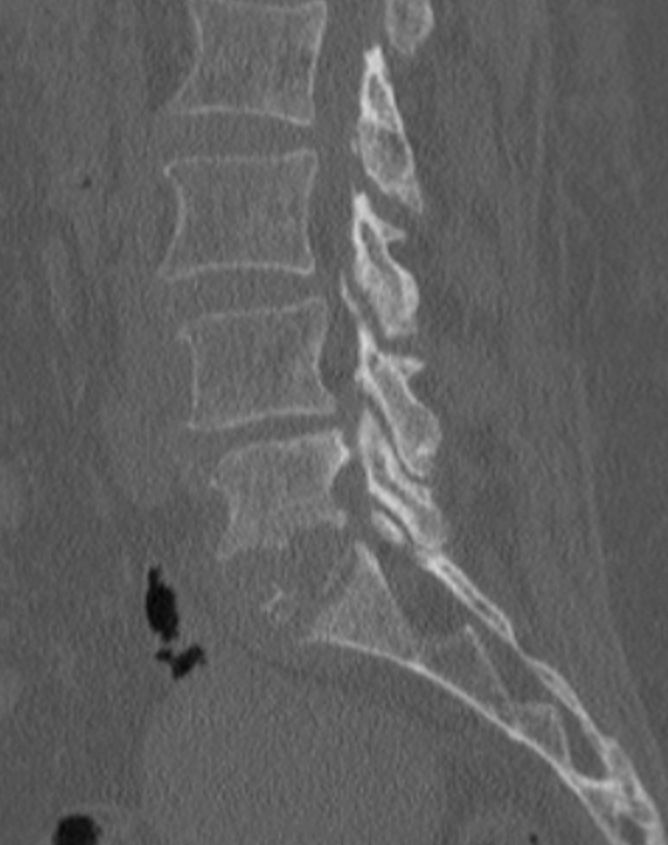

Infective Spondylodiscitis at L5-S1

Imaging studies, including MRI and plain X-rays, confirmed the presence of spondylodiscitis at the L5-S1 level, characterized by destruction of the vertebral end plates and narrowing of the intervertebral disc space. There were also early signs of instability at the lumbosacral junction. The progressive bony destruction was concerning, as it posed risks of persistent pain, deformity, and potential neurological compromise if left untreated. The combination of advanced age, severe functional disability, and the destructive changes necessitated surgical management. A plan for posterior instrumentation with stabilization, debridement, and bone grafting was made to control infection, restore stability, and promote fusion.